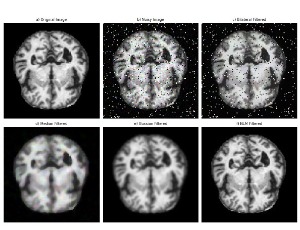

Efficient Alzheimer’s disease classification using transfer learning with efficientNetV2S

Alzheimer’s disease (AD) is a progressive neurodegenerative disorder that affects millions of individuals worldwide, leading to memory loss, cognitive decline, and functional impairments. Early and accurate detection of AD is critical for effective management and treatment planning. This paper presents an efficient approach for Alzheimer’s disease classification using a deep learning model based on the EfficientNetV2S architecture, leveraging transfer learning to enhance performance.